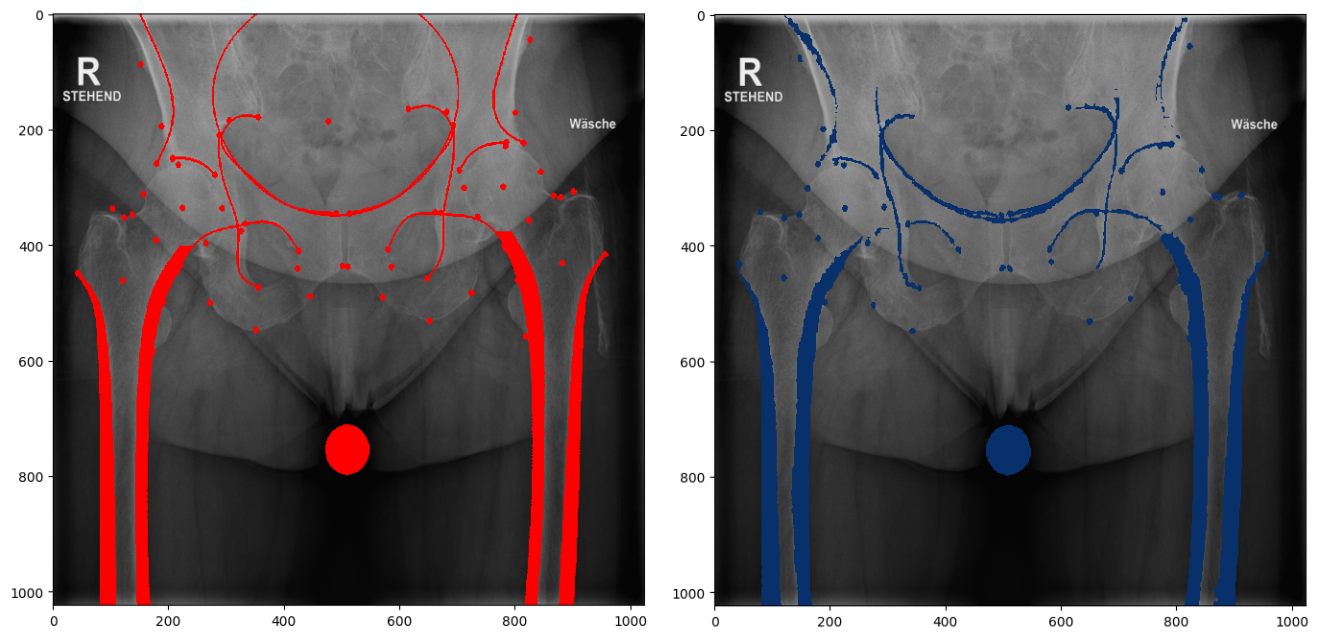

For the scaled problem, the landmarks were defined as circles of 2 mm radius. An outline is an orthopaedic line, created by the superimposition of 3D features on a radiograph. Patches fill in cortical bone of the left and right femora and the calibration ball in the middle. Some of the features overlap in part (Fig. 7).

Refer to caption

Figure 7: Ground truth data, bounding boxes, landmarks, outlines and patches.